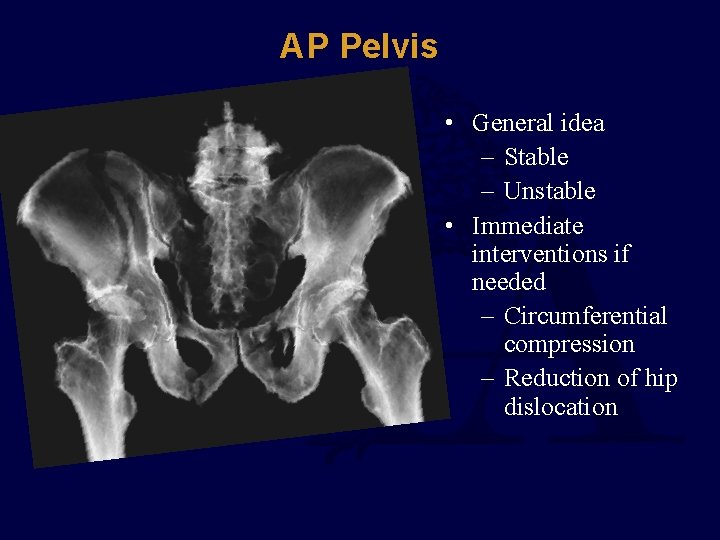

AP Pelvis • General idea – Stable – Unstable • Immediate interventions if needed – Circumferential compression – Reduction of hip dislocation